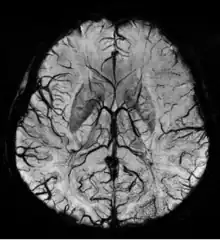

Susceptibility weighted imaging (SWI), originally called BOLD venographic imaging, is an MRI sequence that is exquisitely sensitive to venous blood, hemorrhage and iron storage. SWI uses a fully flow compensated, long echo, gradient recalled echo (GRE) pulse sequence to acquire images. This method exploits the susceptibility differences between tissues and uses the phase image to detect these differences. The magnitude and phase data are combined to produce an enhanced contrast magnitude image. The imaging of venous blood with SWI is a blood-oxygen-level dependent (BOLD) technique which is why it was (and is sometimes still) referred to as BOLD venography. Due to its sensitivity to venous blood SWI is commonly used in traumatic brain injuries (TBI) and for high resolution brain venographies but has many other clinical applications. SWI is offered as a clinical package by Philips and Siemens but can be run on any manufacturer's machine at field strengths of 1.0 T, 1.5 T, 3.0 T and higher.